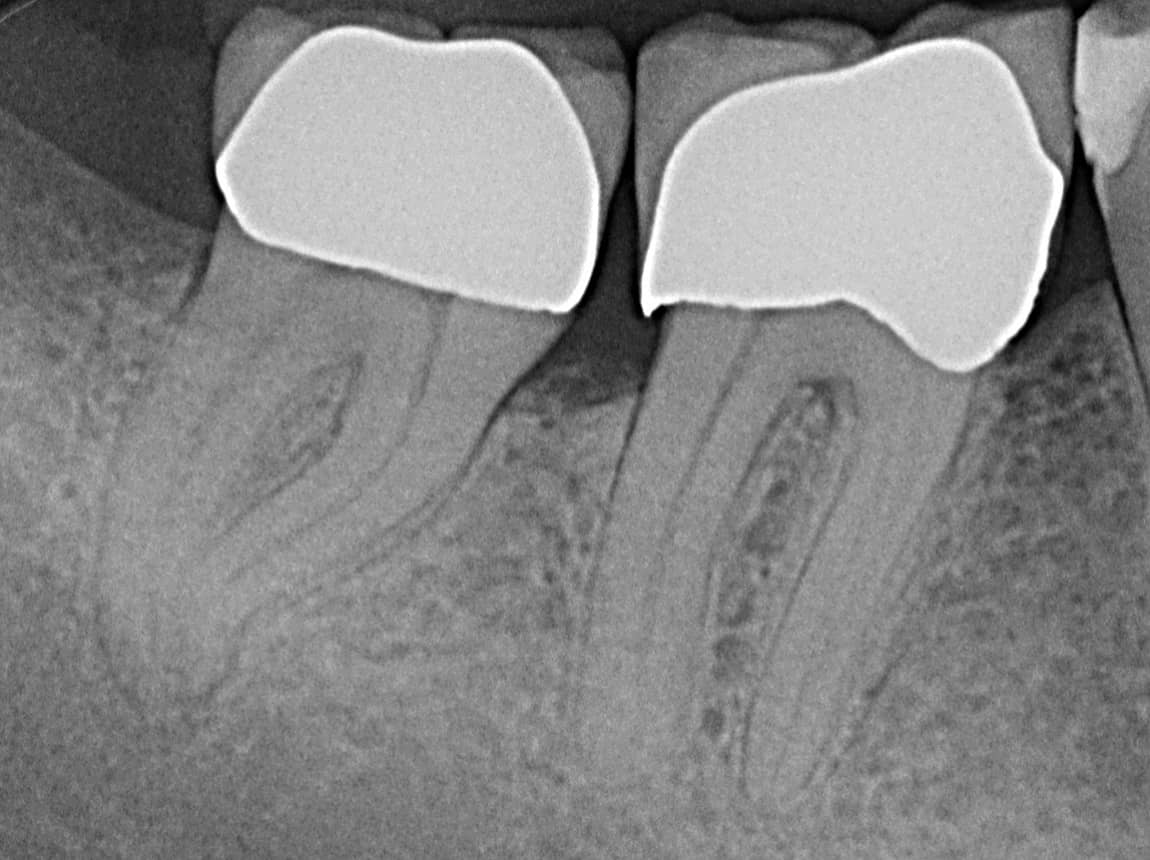

Ist der Defekt zu tief oder der Nerv im Zahn abgestorben, ist vorher eine Wurzelkanalbehandlung notwendig. Dabei wird der Hohlraum im Zahn gesäubert, desinfiziert und anschließend mit Guttapercha versiegelt. Das Ganze erfolgt in unserer Praxis in der Regel mittels moderner maschineller Aufbereitung und durch suffiziente Lokalanästhesie können unnötige Schmerzen verhindert werden.